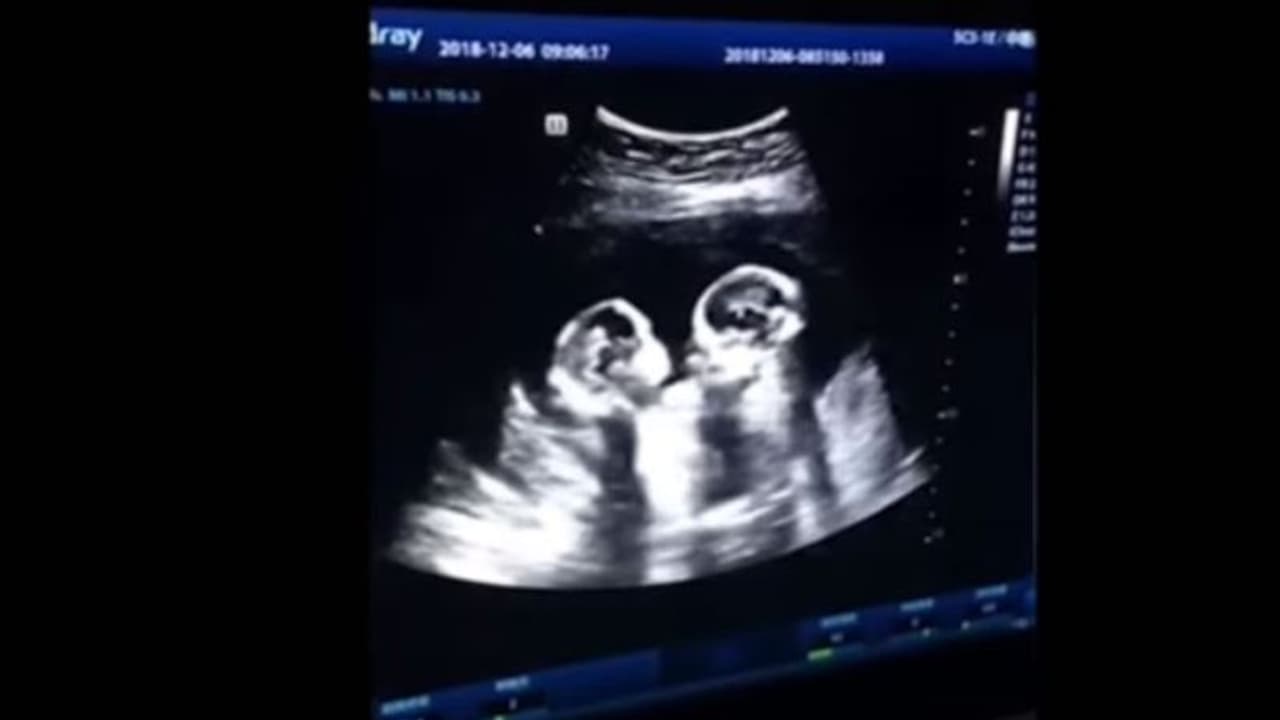

സഹോദരങ്ങള് തമ്മിലുള്ള ഈ 'ശത്രുത' ഗര്ഭപാത്രത്തില് നിന്നേ തുടങ്ങുന്നുവെന്നാണ് ഇപ്പോള് വൈറലായിക്കൊണ്ടിരിക്കുന്ന ഒരു വീഡിയോ തെളിയിക്കുന്നത്. അമ്മയുടെ ഗര്ഭപാത്രത്തില് കിടക്കുന്ന ഇരട്ടക്കുഞ്ഞുങ്ങള് തമ്മില് അടികൂടുന്നതിന്റെ സ്കാനിംഗ് ദൃശ്യങ്ങളാണ് കയ്യടികളേറ്റുവാങ്ങി സമൂഹമാധ്യമങ്ങളില് ഓടിക്കൊണ്ടിരിക്കുന്നത്.

ചൈനയിലെ യിന്ചുവാനിലുള്ള ആശുപത്രിയില് കഴിഞ്ഞ ഡിസംബറില് നടന്ന സ്കാനിംഗിന്റെ ദൃശ്യങ്ങളാണ് ഇപ്പോള് പുറത്തുവന്നിരിക്കുന്നത്. യുവതിയുടെ ഭര്ത്താവാണ് സ്കാനിംഗ് മോണിട്ടറില് കണ്ട അത്യപൂര്വ്വമായ ദൃശ്യങ്ങള് ഷൂട്ട് ചെയ്ത് പുറത്തുവിട്ടത്.

കുഞ്ഞുങ്ങള് മുഖാമുഖം കിടന്ന് രണ്ട് മുതിര്ന്ന ആളുകളെ പോലെ വഴക്ക് കൂടുന്നതാണ് ദൃശ്യങ്ങളിലുള്ളത്. ജനുവരിയില് വീണ്ടും സ്കാനിംഗ് നടത്തിയപ്പോള് സീന് ആകെ മാറി. രണ്ടുപേരും പരസ്പരം കെട്ടിപ്പിടിച്ച് സ്നേഹമായിരിക്കുന്നു. എന്താായാലും ഏപ്രില് എട്ടോടെ, അല്പസ്വല്പം പ്രശ്നങ്ങളെല്ലാം സൃഷ്ടിച്ച്, സിസേറിയനിലൂടെ ഇരട്ട പെണ്കുഞ്ഞുങ്ങള് പുറത്തുവന്നു.